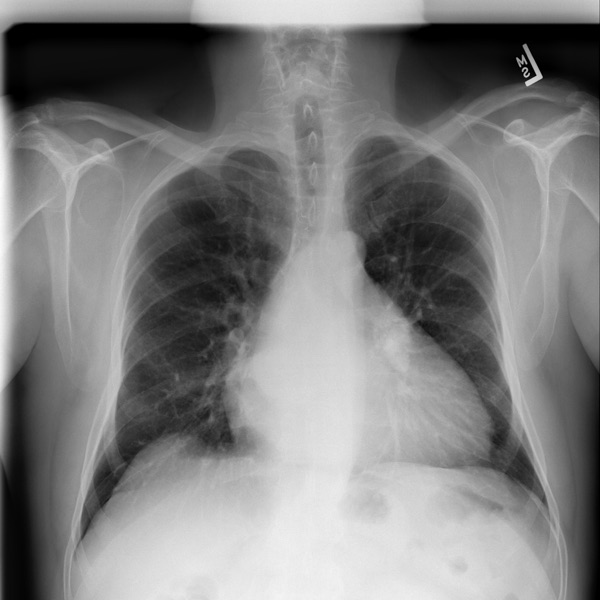

Can AI write radiology reports from chest X-rays?

A subset of the full ReXrank evaluation suite